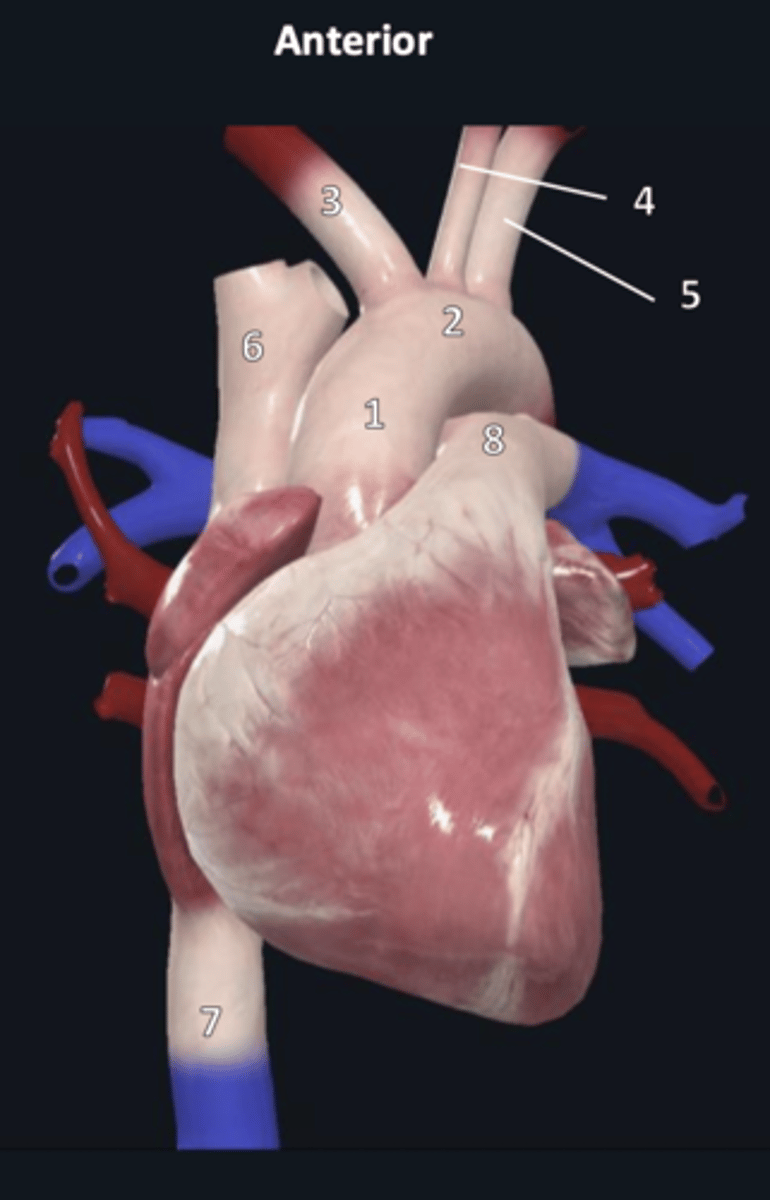

ascending aorta

1

aortic arch

2

brachiocephalic trunk

3

left common carotid artery

4

left subclavian artery

5

superior vena cava

6

inferior vena cava

7

pulmonary trunk

8